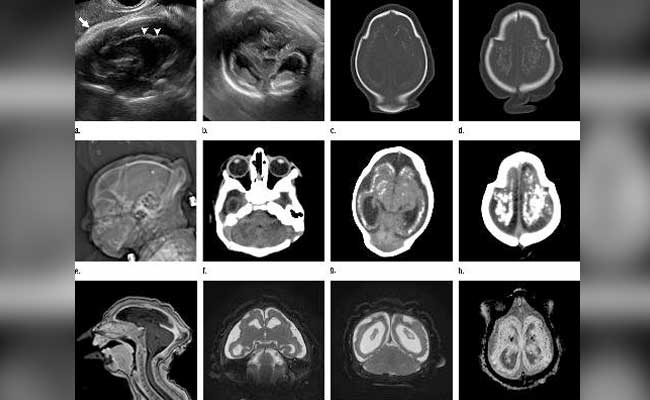

A report released on Tuesday shows in graphic detail the kind of damage Zika infections can do to the developing brain - damage that goes well beyond the devastating birth defect known as microcephaly, in which the baby's head is smaller than normal.